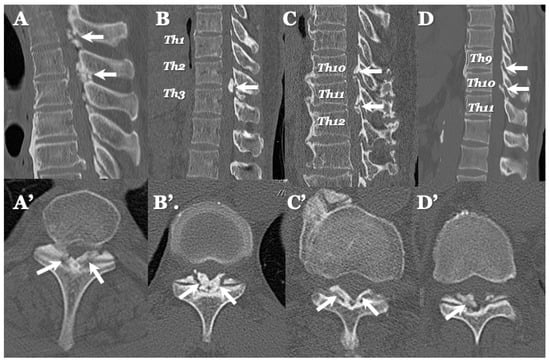

3.3. Neuroradiological Findings (Figure 3, Figure 4, Figure 5 and Figure 6; Table 3)

4.2. Comparison of Neuroradiological Findings between CLF and OLF (Figure 3, Figure 4, Figure 5 and Figure 6; Table 3)